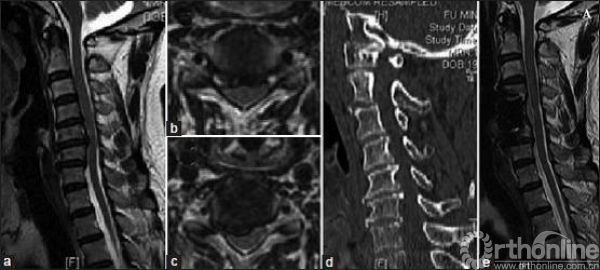

图1 A. 男性,41岁,诊断为近端型CSA,并接受颈椎前路减压融合术。(a)MRT2矢状位图像显示C4-5、C5-6节段脊髓受压;(b)MRT2横断面显示C4-5节段脊髓前方中央型受压;(c)MRT2横断面显示C5-6节段脊髓前角受损;(d)CT矢状位二维重建提示颈椎管伴有狭窄;(e)术后1年MRT2图像,椎体次全切除区域脊髓获得充分减压,其他节段也无任何压迫。